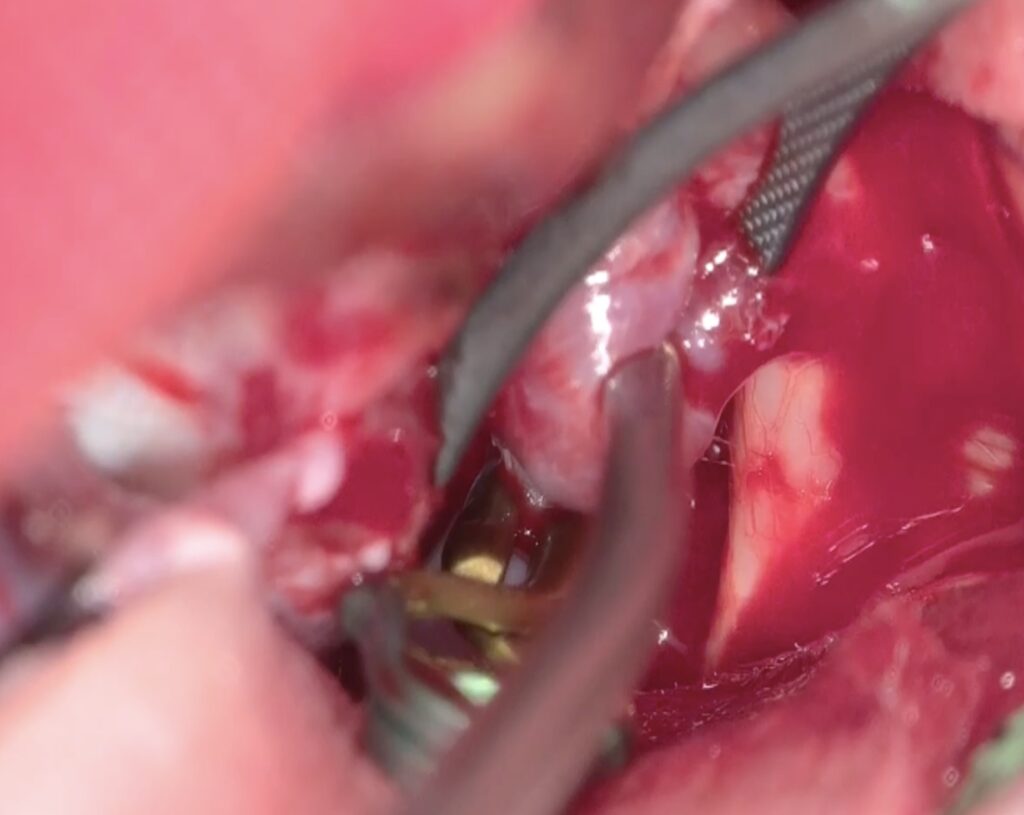

最近のこの場所の動脈瘤クリッピング術が増えています。4mm以上の上向き動脈瘤で術前BTOで虚血耐性のあるものを適応としています。ICG、MEP、VEG、術中血管撮影など術中画像、電気生理学モニタリングをしっかり準備して行っています。本例も視神経下面と癒着しており、剥がすときに破れましたが、問題なくクリップできています。術後の視機能も良好でした。

術後嗄声と2/23より髄液鼻漏れがあり、CTで左篩骨洞に髄液貯留があり5日間の腰椎ドレナージを行い、治癒しました。